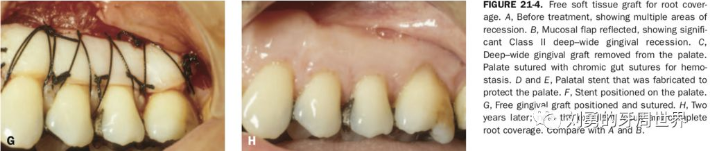

對于需要進(jìn)行根面覆蓋的手術(shù),移植瓣需要縫合固定到CEJ冠向1mm左右的位置。如下圖: